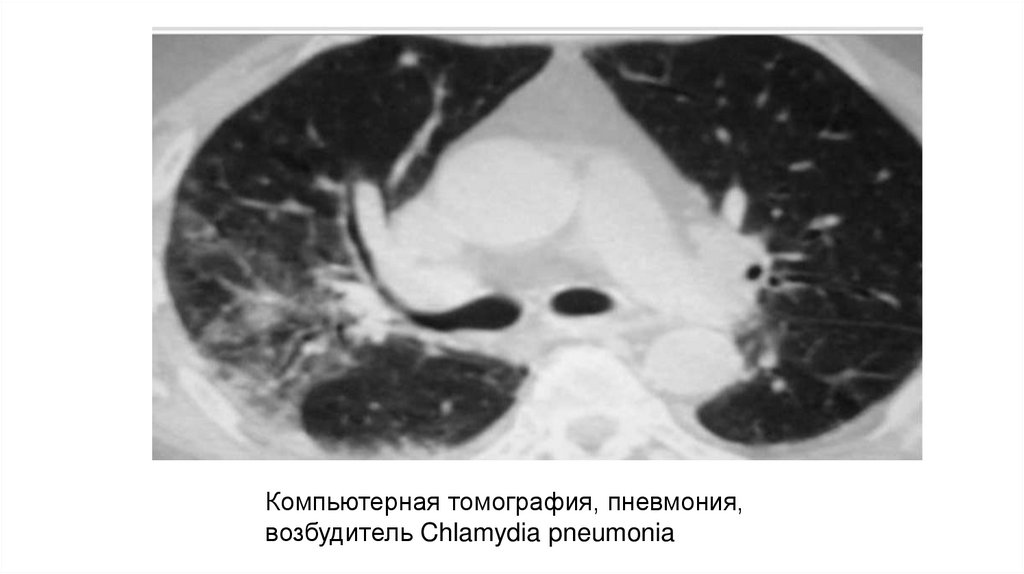

Компьютерная томография, пневмония,

возбудитель Chlamydia pneumonia